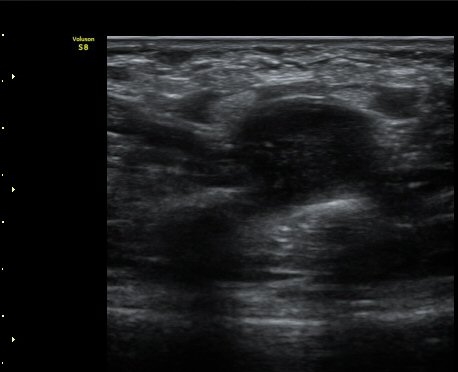

ŽÃËÀÚ¸¦ ¸»´ÜÀ¸·Î À̵¿ÇÏ´Ï °¥°í¸®»À ³»Ãø¿¡¼­ Ç¥Ãþ°¨°¢½Å°æ°ú ½ÉºÎ¿îµ¿½Å°æÀÌ °üÂûµÈ´Ù(»çÁø 3).